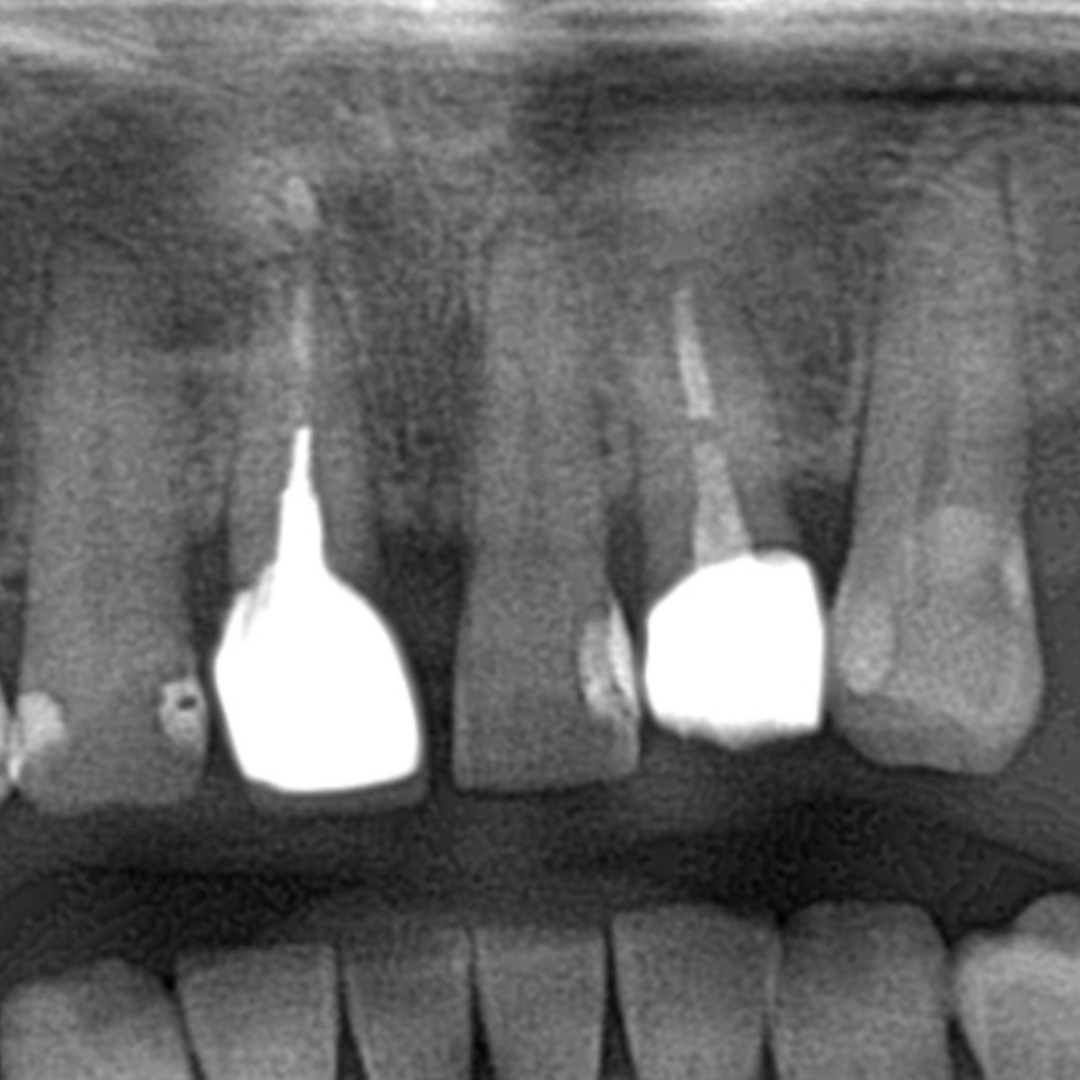

Aspectul radiologic dupa tratamentul de canal, inserarea pivotului si cimentarea coroanei definitive.